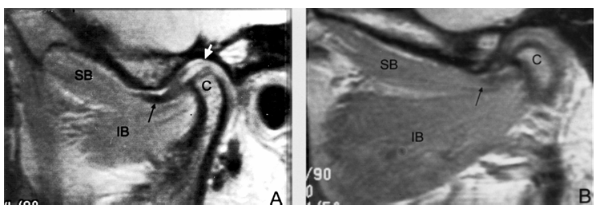

Example of TMJ on 50 Year-Old Woman:

Above is a picture of the left and right TMJ of a 50-year old woman. On the right (A) the lateral ptyergoid is weakened and atrophied while on the left (B) it is overdeveloped. They both can cause significant pain. In our office, we focus on treating the muscular imbalance that exists in the joint, restoring strength, reducing spasm and returning it to function. With the restoration of function, the pain associated with chewing usually resides. Dr. Zumpano will NEVER perform a high velocity adjustment to these joints. His treatments restore the proper biomechanial motion into the joint by emphasising manual muscle therapy.